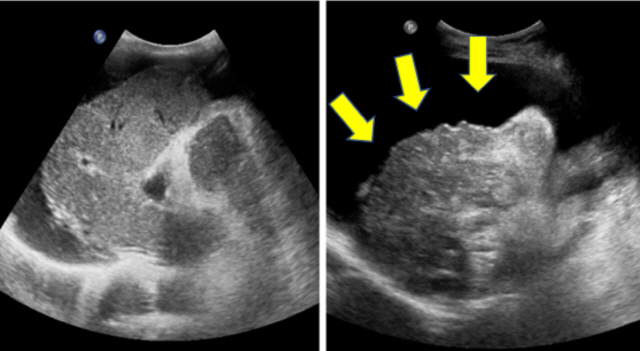

간경화 초기증상으로 간의 섬유화에 따라 조직이 구조변경가 일어나고, 간의 혈청 단백질의 한가지인 알부민의 합성 기능도 저하되게 된다고 합니다. 알부민 합성 기능이 저하되면 알부민이 작게 변하며, 수분이 혈관내에 들어가지 못하고 복부와 손, 발의 피하조직이 부종 증상을 유발하더라고요.

그리고 대장에서 간으로 혈액을 운반하기 위해 문맥이라고 부르는 큰 정맥의 압력이 상승해서 대장에서 간으로 혈액을 수어긋나는 문맥이라고 호출하는 큰 정맥의 압력이 높게되 문맥압 항진증, 림프가 림프절 바깥으로 새어 나오는 경우도 있고요. 이것들이 복부에 새어 나오면 복수가 되어버립니다.

간경화가 어느 정도 진행이 돼서 복수가 차는 증상이 나타나게 되었다면 이뇨제를 동원해 조절하게 됩니다. 하지만 이뇨제를 사용해겠지만 호흡이 곤란하고 복부에 통증이 나타난 경향이라면 복수 천자를 시행하는데, 복수 천자가 가장 빠르고 효과가 좋은 방법이라고 합니다. 복수 천자는 주사기를 활용해서 직접 배에서 복수를 빼내는 방법이라고 할 수 있다하며, 이 방법은 바로 복수가 빠지었으므로 복수로 인한 불편함은 빠르게 해소되지만 잠정적인 방법이라서, 일정 기간이 경화하다 보면 복수는 다시 차게 되기 때문에 복수를 되풀이해서 빼주어야 합니다. 또한 복수가 있는 간경화를 앓는 환자들 중 자발성 세균성 복막염이 생기게 되는 상황가 있다고 하는데, 이 경우에는 항생제를 이용해서 치료하게 되기도 합니다. 세밀한 것은 내방하셔서 전문의와 상의하는 것을 권유해 드려볼께요 할게요.